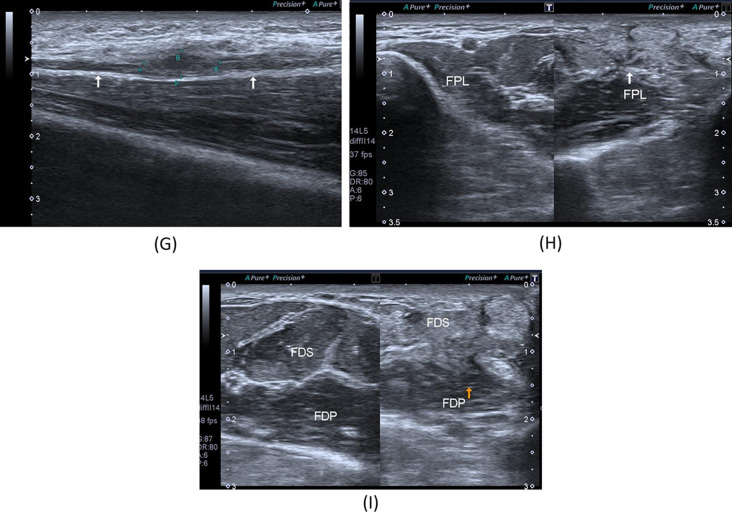

A 28-year- old male patient presenting with history gunshot injury to the left forearm since June 2021. He underwent flexor muscles and tendons in addition to median nerve repair. A Patient’s forearm showing scar tissue. B X-ray image of the left forearm multiple retained bullets. C, D B-mode image, transverse axis, shows thickened median nerve(arrow) at proximal forearm with circumferential hypoechoic lesion. E B-mode image, longitudinal axis, shows intact epineurum of the median nerve(arrows) at proximal forearm with superficially related hypoechoic lesion (oblique arrow). F B-mode image, transverse axis, shows thickened hypoechoic ulnar nerve at proximal forearm. G B-mode image, longitudinal axis, shows thick hypoechoic swelling of the left ulnar nerve with loss of fascicular architecture. H B-mode image, transverse axis, abnormal architecture of the left FPL muscle with increased echogenicity and reduced girth as compared to the normal right side. I B-mode image, transverse axis, abnormal architecture of the left FDS muscle with increased echogenicity and reduced girth as compared to the normal right side